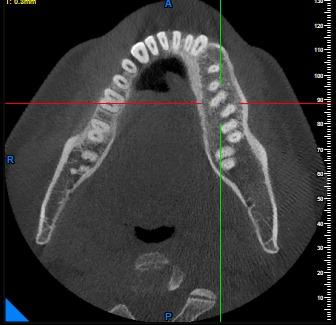

Cyst Diagnosis

Accurately identifies and locates cysts and other pathological lesions within the jaws and surrounding bone structures, aiding in proper treatment planning.

Cyst-Cross Sectional View

Cyst-Orthogonal Plane View